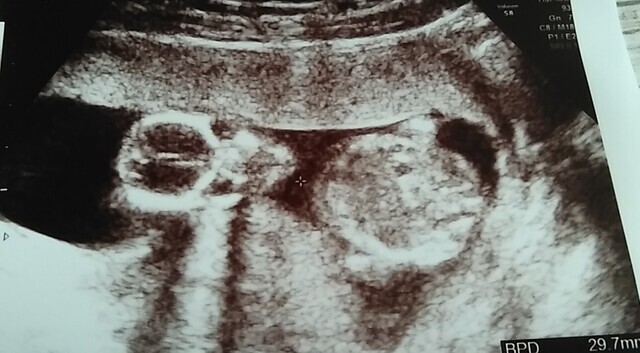

15週6日(15w6d・男の子・双子)|maiiii さん(17歳)

エコー写真撮影時のエピソード:

初めての妊娠。産婦人科に行くと双子ですと言われ、義母さんは信じられないと、もう一回検診しに行きました。やっぱり双子。親戚に双子は居なくてみんな驚きました。

産んでいいって言われてこれからの話し合いをして、毎回の検診には義母さんがついてきてくれました。双子は管理入院もなく、2人とも2キロ越えで立派に生まれてきました。